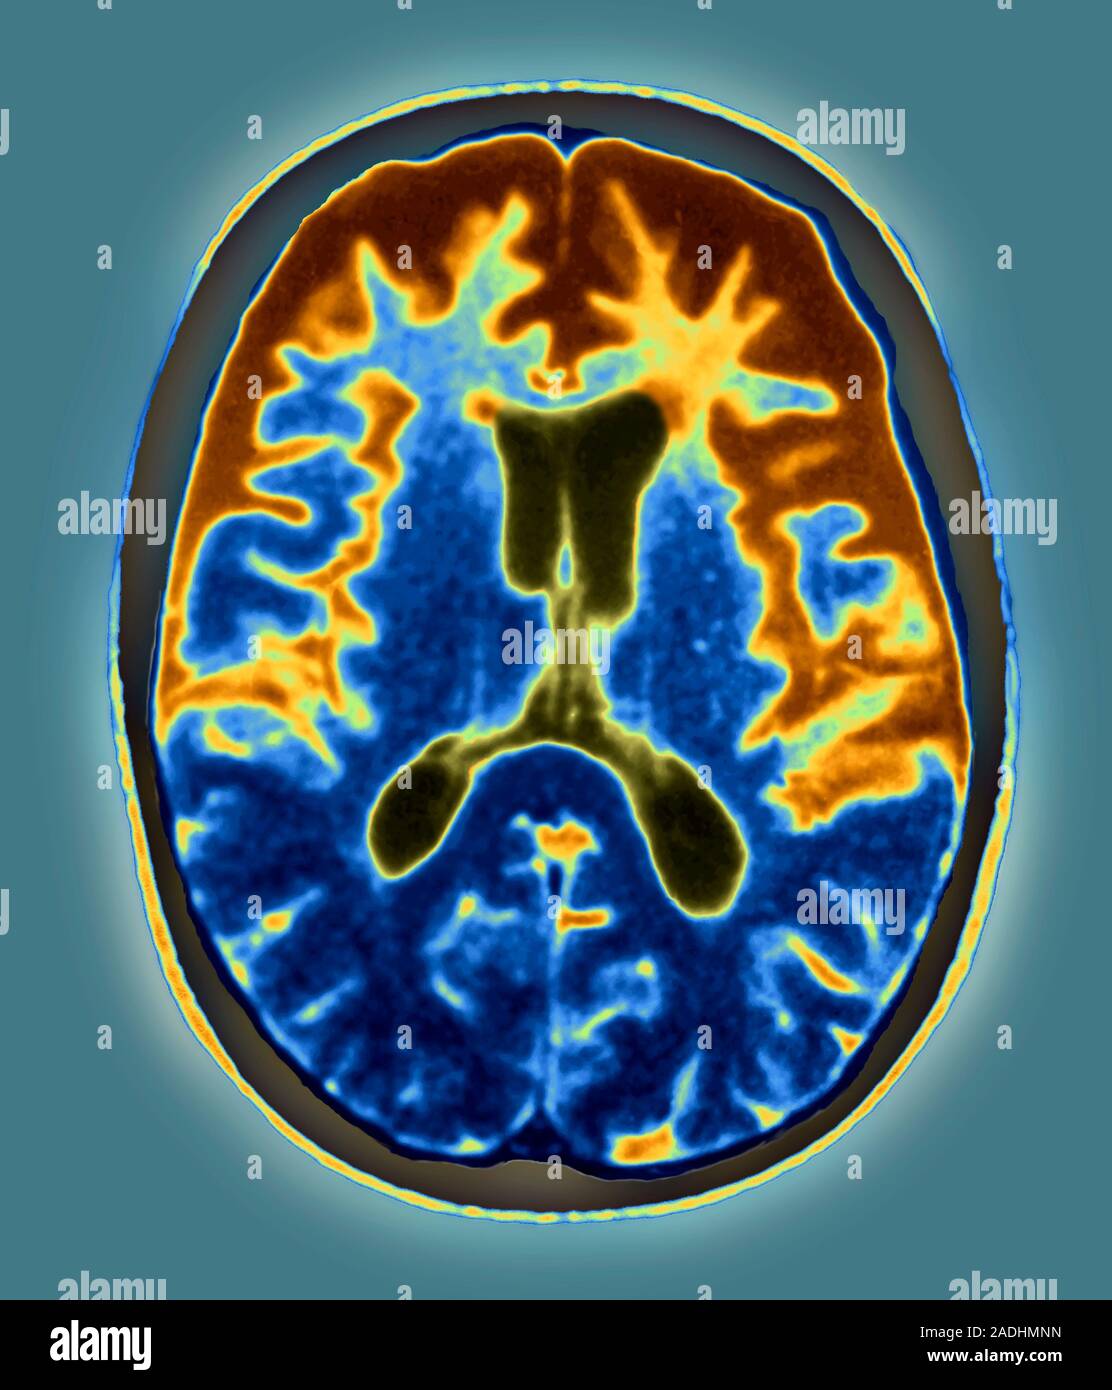

Pick's disease. Coloured axial resonance imaging (MRI) scan of Pick Disease Radiology Mri order a computed tomography (ct) scan if magnetic resonance imaging (mri) is contraindicated in the patient (eg, if the. in this paper, i briefly describe the magnetic resonance imaging (mri) findings in pick disease, progressive nonfluent aphasia,. pick’s disease (pid) is a devastating neurodegenerative disease that is characterized by dementia, frontotemporal. standard, structural magnetic resonance imaging. Pick Disease Radiology Mri.

Pick Disease Radiology Mri . order a computed tomography (ct) scan if magnetic resonance imaging (mri) is contraindicated in the patient (eg, if the. the characteristic features of pick disease include 1 : standard, structural magnetic resonance imaging (mri), and computed tomography (ct) modalities. Loss of large pyramidal neurons. pick’s disease (pid) is a devastating neurodegenerative disease that is characterized by dementia, frontotemporal. in this paper, i briefly describe the magnetic resonance imaging (mri) findings in pick disease, progressive nonfluent aphasia,. frontotemporal lobar degeneration (ftld) is the pathological description of a group of neurodegenerative disorders characterized by. the classic mr pattern of pick’s disease shows frontal and temporal cortical atrophy, prominent enlargement of the frontal and inferior horns of the.

order a computed tomography (ct) scan if magnetic resonance imaging (mri) is contraindicated in the patient (eg, if the. the characteristic features of pick disease include 1 : the classic mr pattern of pick’s disease shows frontal and temporal cortical atrophy, prominent enlargement of the frontal and inferior horns of the. standard, structural magnetic resonance imaging (mri), and computed tomography (ct) modalities. Loss of large pyramidal neurons. in this paper, i briefly describe the magnetic resonance imaging (mri) findings in pick disease, progressive nonfluent aphasia,. pick’s disease (pid) is a devastating neurodegenerative disease that is characterized by dementia, frontotemporal. frontotemporal lobar degeneration (ftld) is the pathological description of a group of neurodegenerative disorders characterized by.